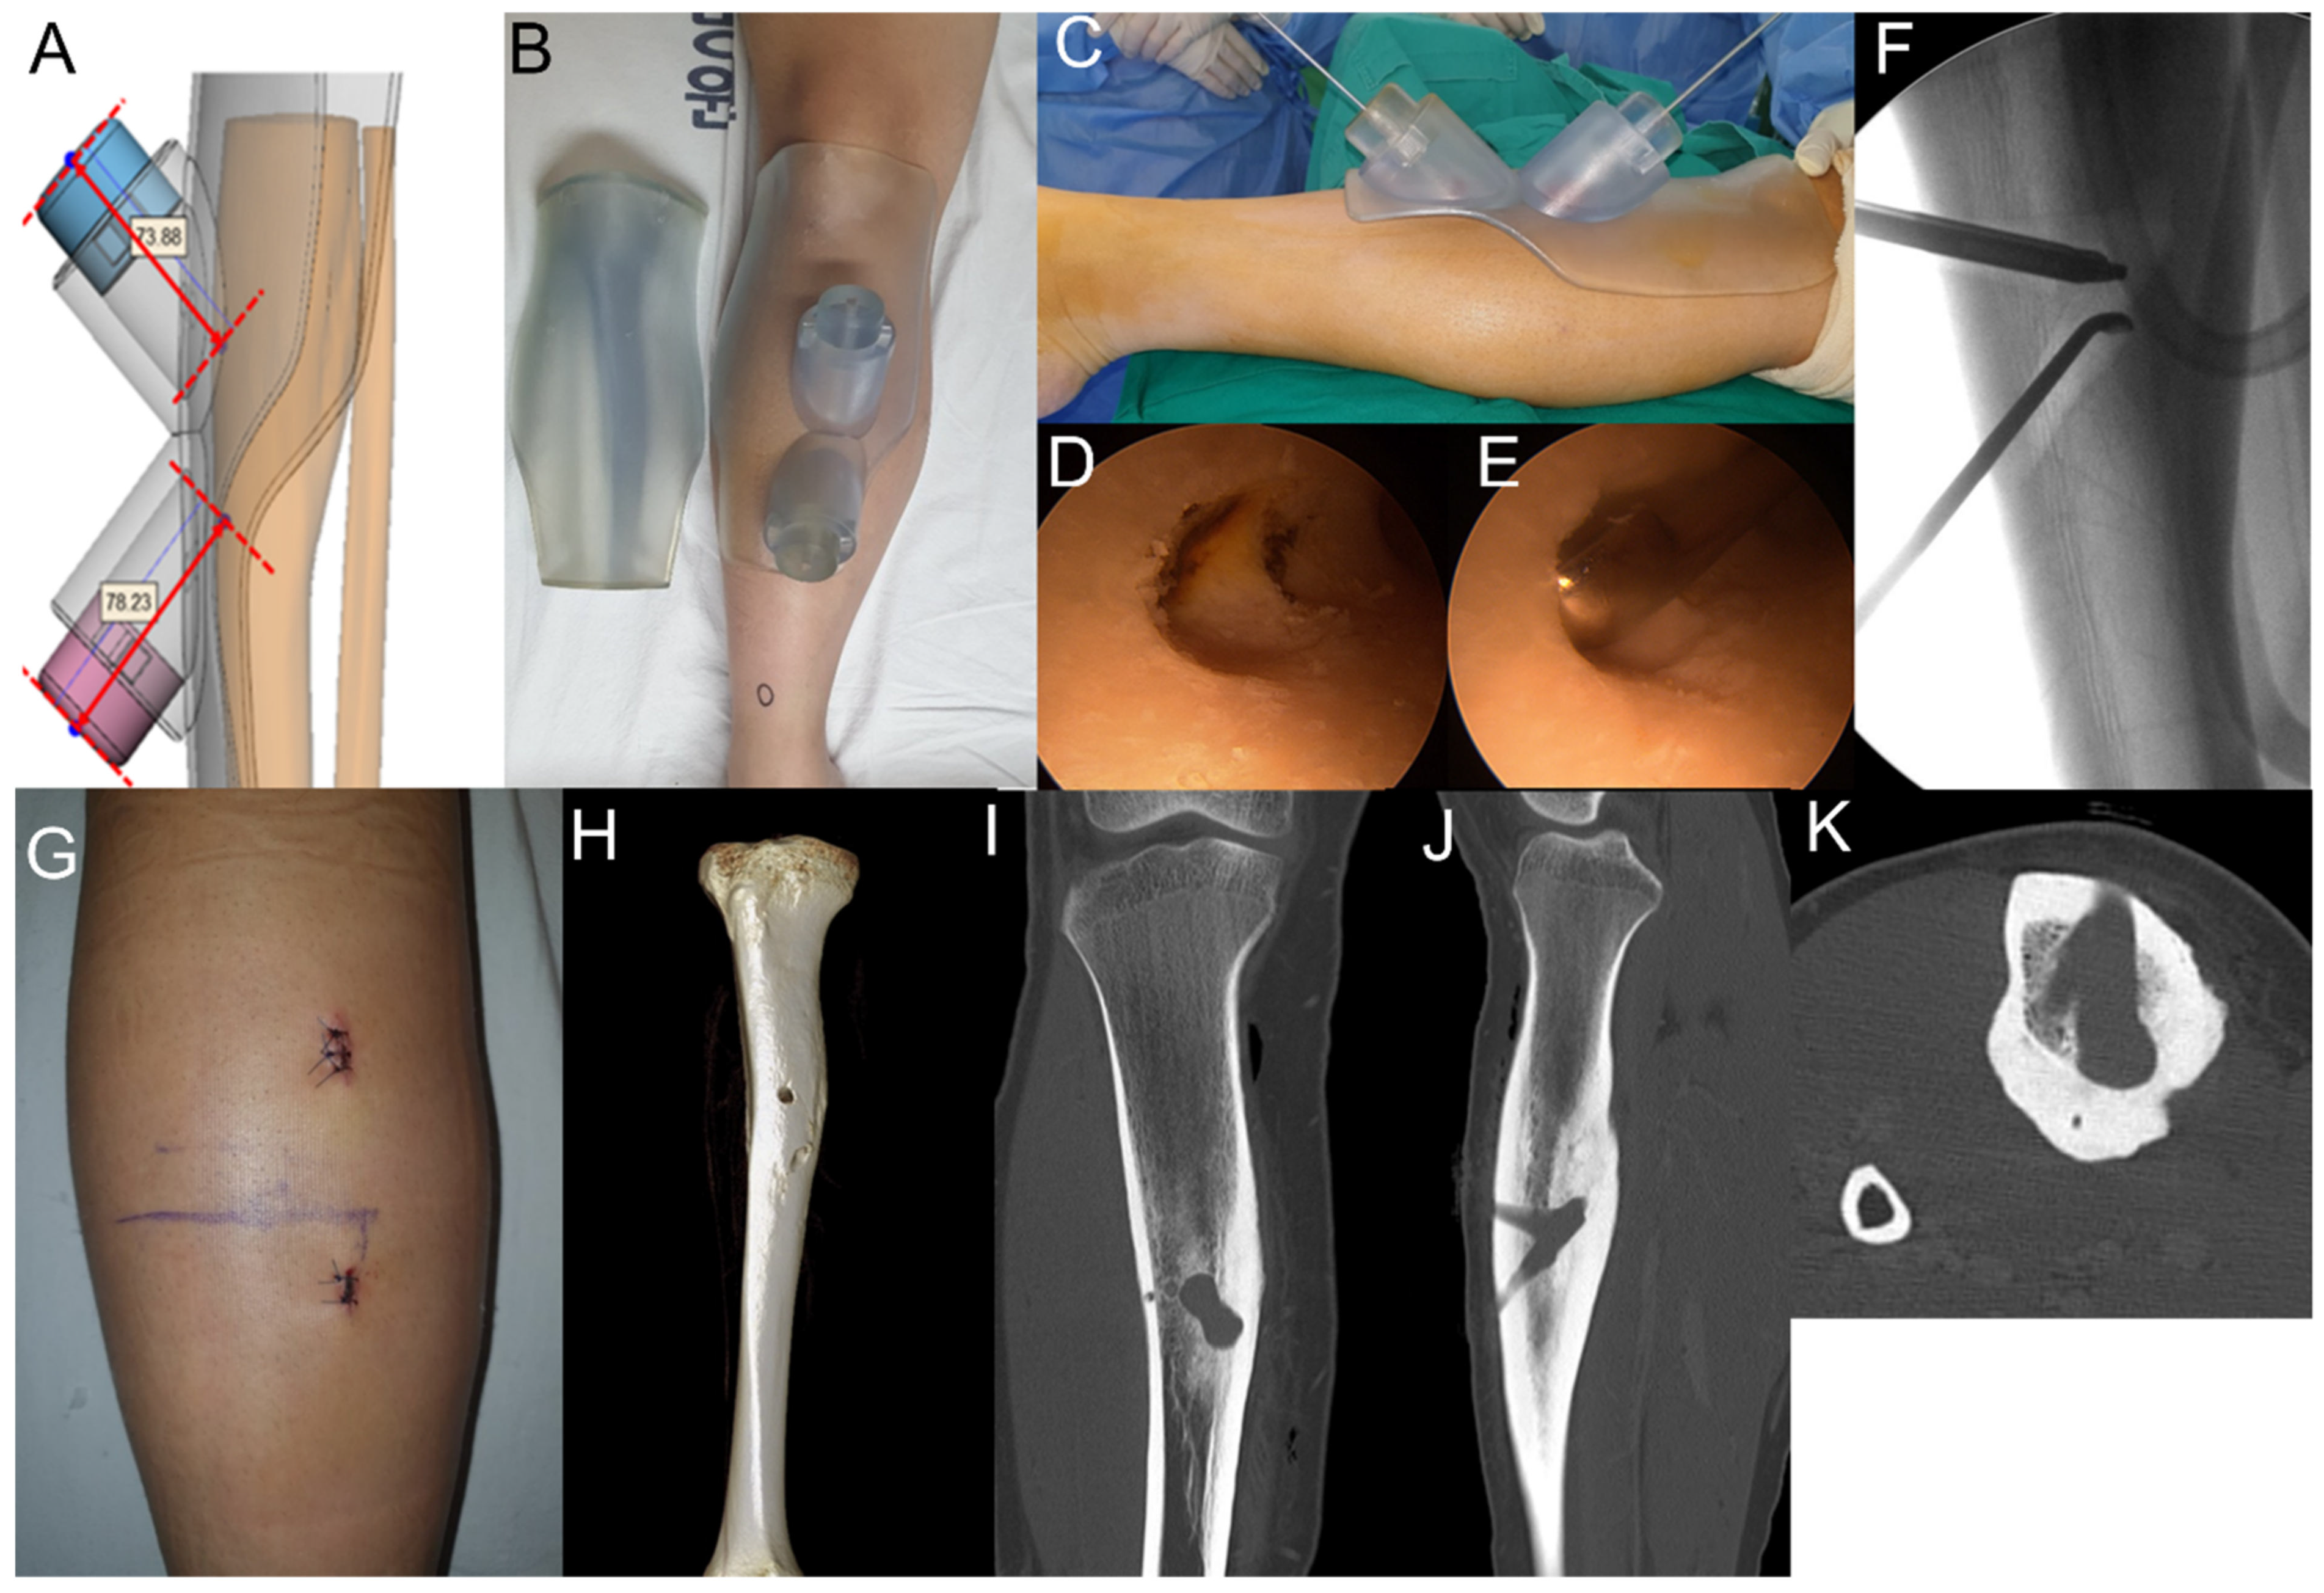

Excision of Intramedullary Osteoid Osteomas in the Posterior Tibial Area via Medulloscopy: A Case Report

2. Case Presentations

2.1. Case 1

2.2. Case 2